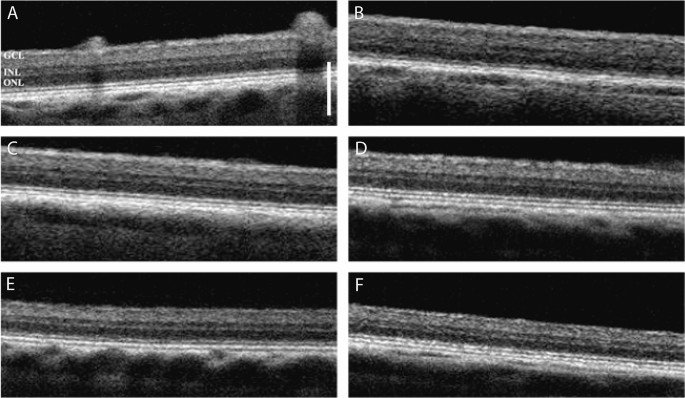

Optical coherence tomography

We initially performed a spectral domain-optical coherence tomography (SD-OCT) analysis to verify the normal health state of the retina in all experimental animals. No morphological retinal abnormalities were observed as SD-OCT scans revealed full integrity (Fig. 1).

Representative optical coherence tomography (OCT) scans of the right eye in each experimental pig (A–F). The images show no morphological alterations of the retina. GCL, ganglion cell layer; INL, inner nuclear layer; ONL, outer nuclear layer. The structural organization of the retina is normal in all experimental animals. Scale bar, 250 µm.